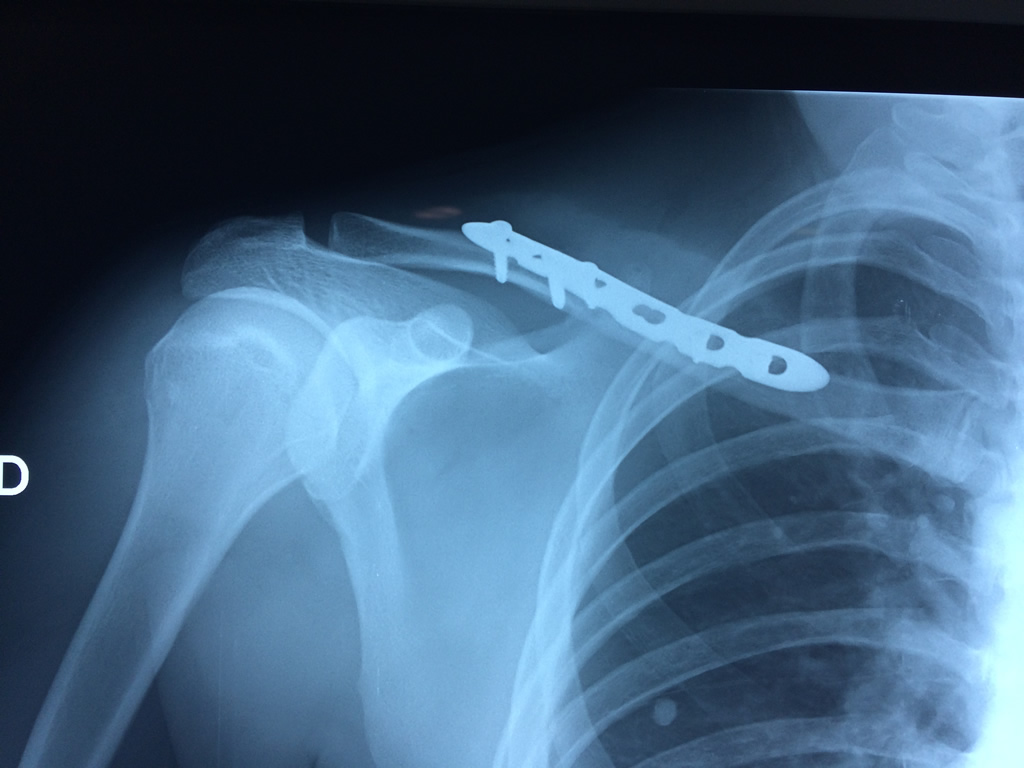

Cirugías de Codos - Clavícula

La clavícula es un hueso largo, con forma de "S" itálica, situado en la parte anterosuperior del tórax. Junto con la escápula forman la cintura escapular. Se puede palpar por toda su longitud y se extiende del esternón al acromion de la escápula, siguiendo una dirección oblicua lateral y posterior.

Se considera el único medio de unión entre el miembro superior y el tórax. A pesar de su aspecto, similar al de un hueso largo, posee una estructura semejante a la de un hueso plano, ya que carece de epífisis y de diáfisis, lo que la harían entrar dentro de la clasificación de hueso largo. Carece de un canal medular propiamente dicho.